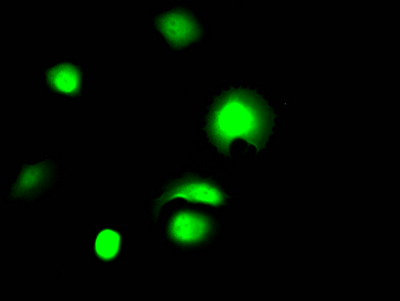

● 雙靶點CAR-NK細胞療法(QN-139b):全球首例由徐滬濟團隊應用于dcSSc的突破性療法。靶向CD19/BCMA雙抗原,通過iPSC來源的CAR-NK細胞清除致病B細胞和漿細胞,誘導免疫重建。